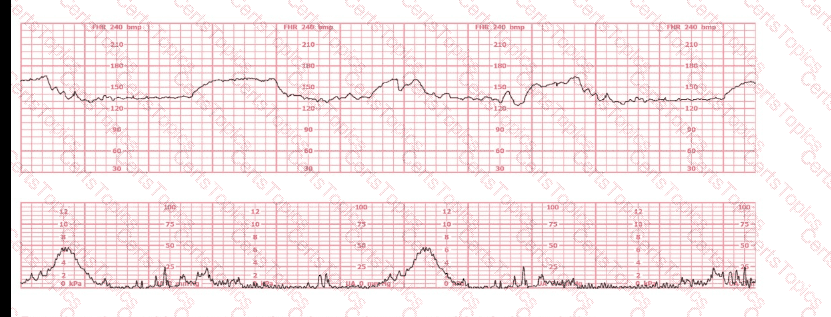

A nulliparous woman at term presents with leaking fluid. Rupture of membranes confirmed. After 6 hours she is completely dilated, +2 station, has been pushing 2 hours with oxytocin at 10 mU/min. The fetal tracing is shown. What is the next step in management?

A woman in labor has been pushing for 4 hours. For the last 2 hours, there have been recurrent variable decelerations. Variability has evolved from moderate to minimal. Cervical exam is 10/100%/+2, fetal head OP. There has been no fetal descent for the last 45 minutes. Based on the tracing shown, the most reasonable approach is

Based on the fetal heart rate tracing shown, the expected fetal pH would be:

Based on the tracing shown, the first action should be to